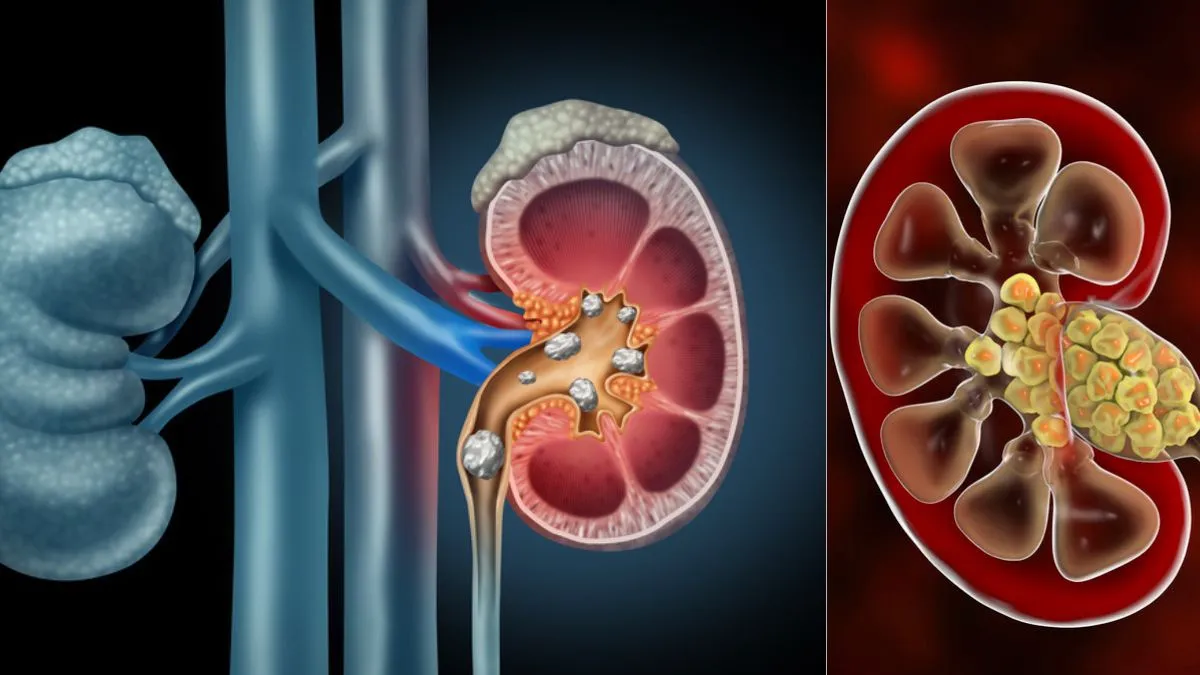

சிறுநீரகம் நமது உடலின் ஒரு முக்கியமான உறுப்பு, இதன் முக்கிய செயல்பாடு இரத்தத்தை சுத்திகரித்து சிறுநீரை உற்பத்தி செய்வதாகும். இது தவிர, நாம் உட்கொள்ளும் உணவுகள் மற்றும் பானங்களில் இருந்து நச்சுகளை அகற்ற சிறுநீரகம் செயல்படுகிறது. ஆனால் இந்த நச்சுகள் சிறுநீரகத்திலிருந்து முழுமையாக அகற்றப்படாவிட்டால், அவை படிப்படியாகக் குவிந்து கற்களாக மாறும். இந்தப் பிரச்சினைக்கு சரியான நேரத்தில் சிகிச்சையளிக்கப்படாவிட்டால், கற்கள் சிறுநீரகத்திற்கு கடுமையான சேதத்தை ஏற்படுத்தும், இது சிறுநீரக செயலிழப்பையும் ஏற்படுத்தும்.

சிறுநீரகக் கற்கள் கூர்மையான மற்றும் கடுமையான வலியை ஏற்படுத்தும், இது குறிப்பாக முதுகு, வயிறு மற்றும் கீழ் முதுகில் உணரப்படுகிறது. கல் சிறுநீர் பாதையில் நுழையும் போது, அது சிறுநீர் குழாய்களைத் தடுத்து, சிறுநீர் கழிப்பதை கடினமாக்குகிறது மற்றும் சிறுநீரகங்களில் அழுத்தத்தை அதிகரிக்கிறது. இந்த வலி மிகவும் தாங்க முடியாததாக இருக்கும், மேலும் சில சமயங்களில் நோயாளி வலி காரணமாக வசதியாக உட்காரவோ அல்லது படுத்துக்கொள்ளவோ சிரமப்படுகிறார். சிறுநீர்க் குழாயில் கல் சிக்கிக்கொள்ளும்போது, வலி இன்னும் அதிகரிக்கும், இது பெரும்பாலும் "கோலிக்கி வலி" என்று அழைக்கப்படுகிறது.

சிறுநீரகக் கற்களின் மிகவும் பொதுவான மற்றும் ஆபத்தான அறிகுறிகளில் ஒன்று சிறுநீரில் இரத்தம், இது ஹெமாட்டூரியா என்று அழைக்கப்படுகிறது. இந்த நிலையில், சிறுநீர் சிவப்பு, இளஞ்சிவப்பு அல்லது பழுப்பு நிறமாக மாறக்கூடும், மேலும் சில சமயங்களில் இரத்தத்தின் அளவு மிகவும் சிறியதாக இருப்பதால் அதை நுண்ணோக்கி இல்லாமல் பார்க்க முடியாது. சிறுநீரகக் கல் துண்டுகள் சிறுநீர் பாதையில் தேய்ப்பதால் இரத்தப்போக்கு ஏற்படுகிறது. இந்த நிலை தீவிரமாக இருக்கலாம், சரியான நேரத்தில் சிகிச்சையளிக்கப்படாவிட்டால், இரத்தப்போக்கு அதிகரித்து, பிற உடல்நலப் பிரச்சினைகளை ஏற்படுத்தும்.